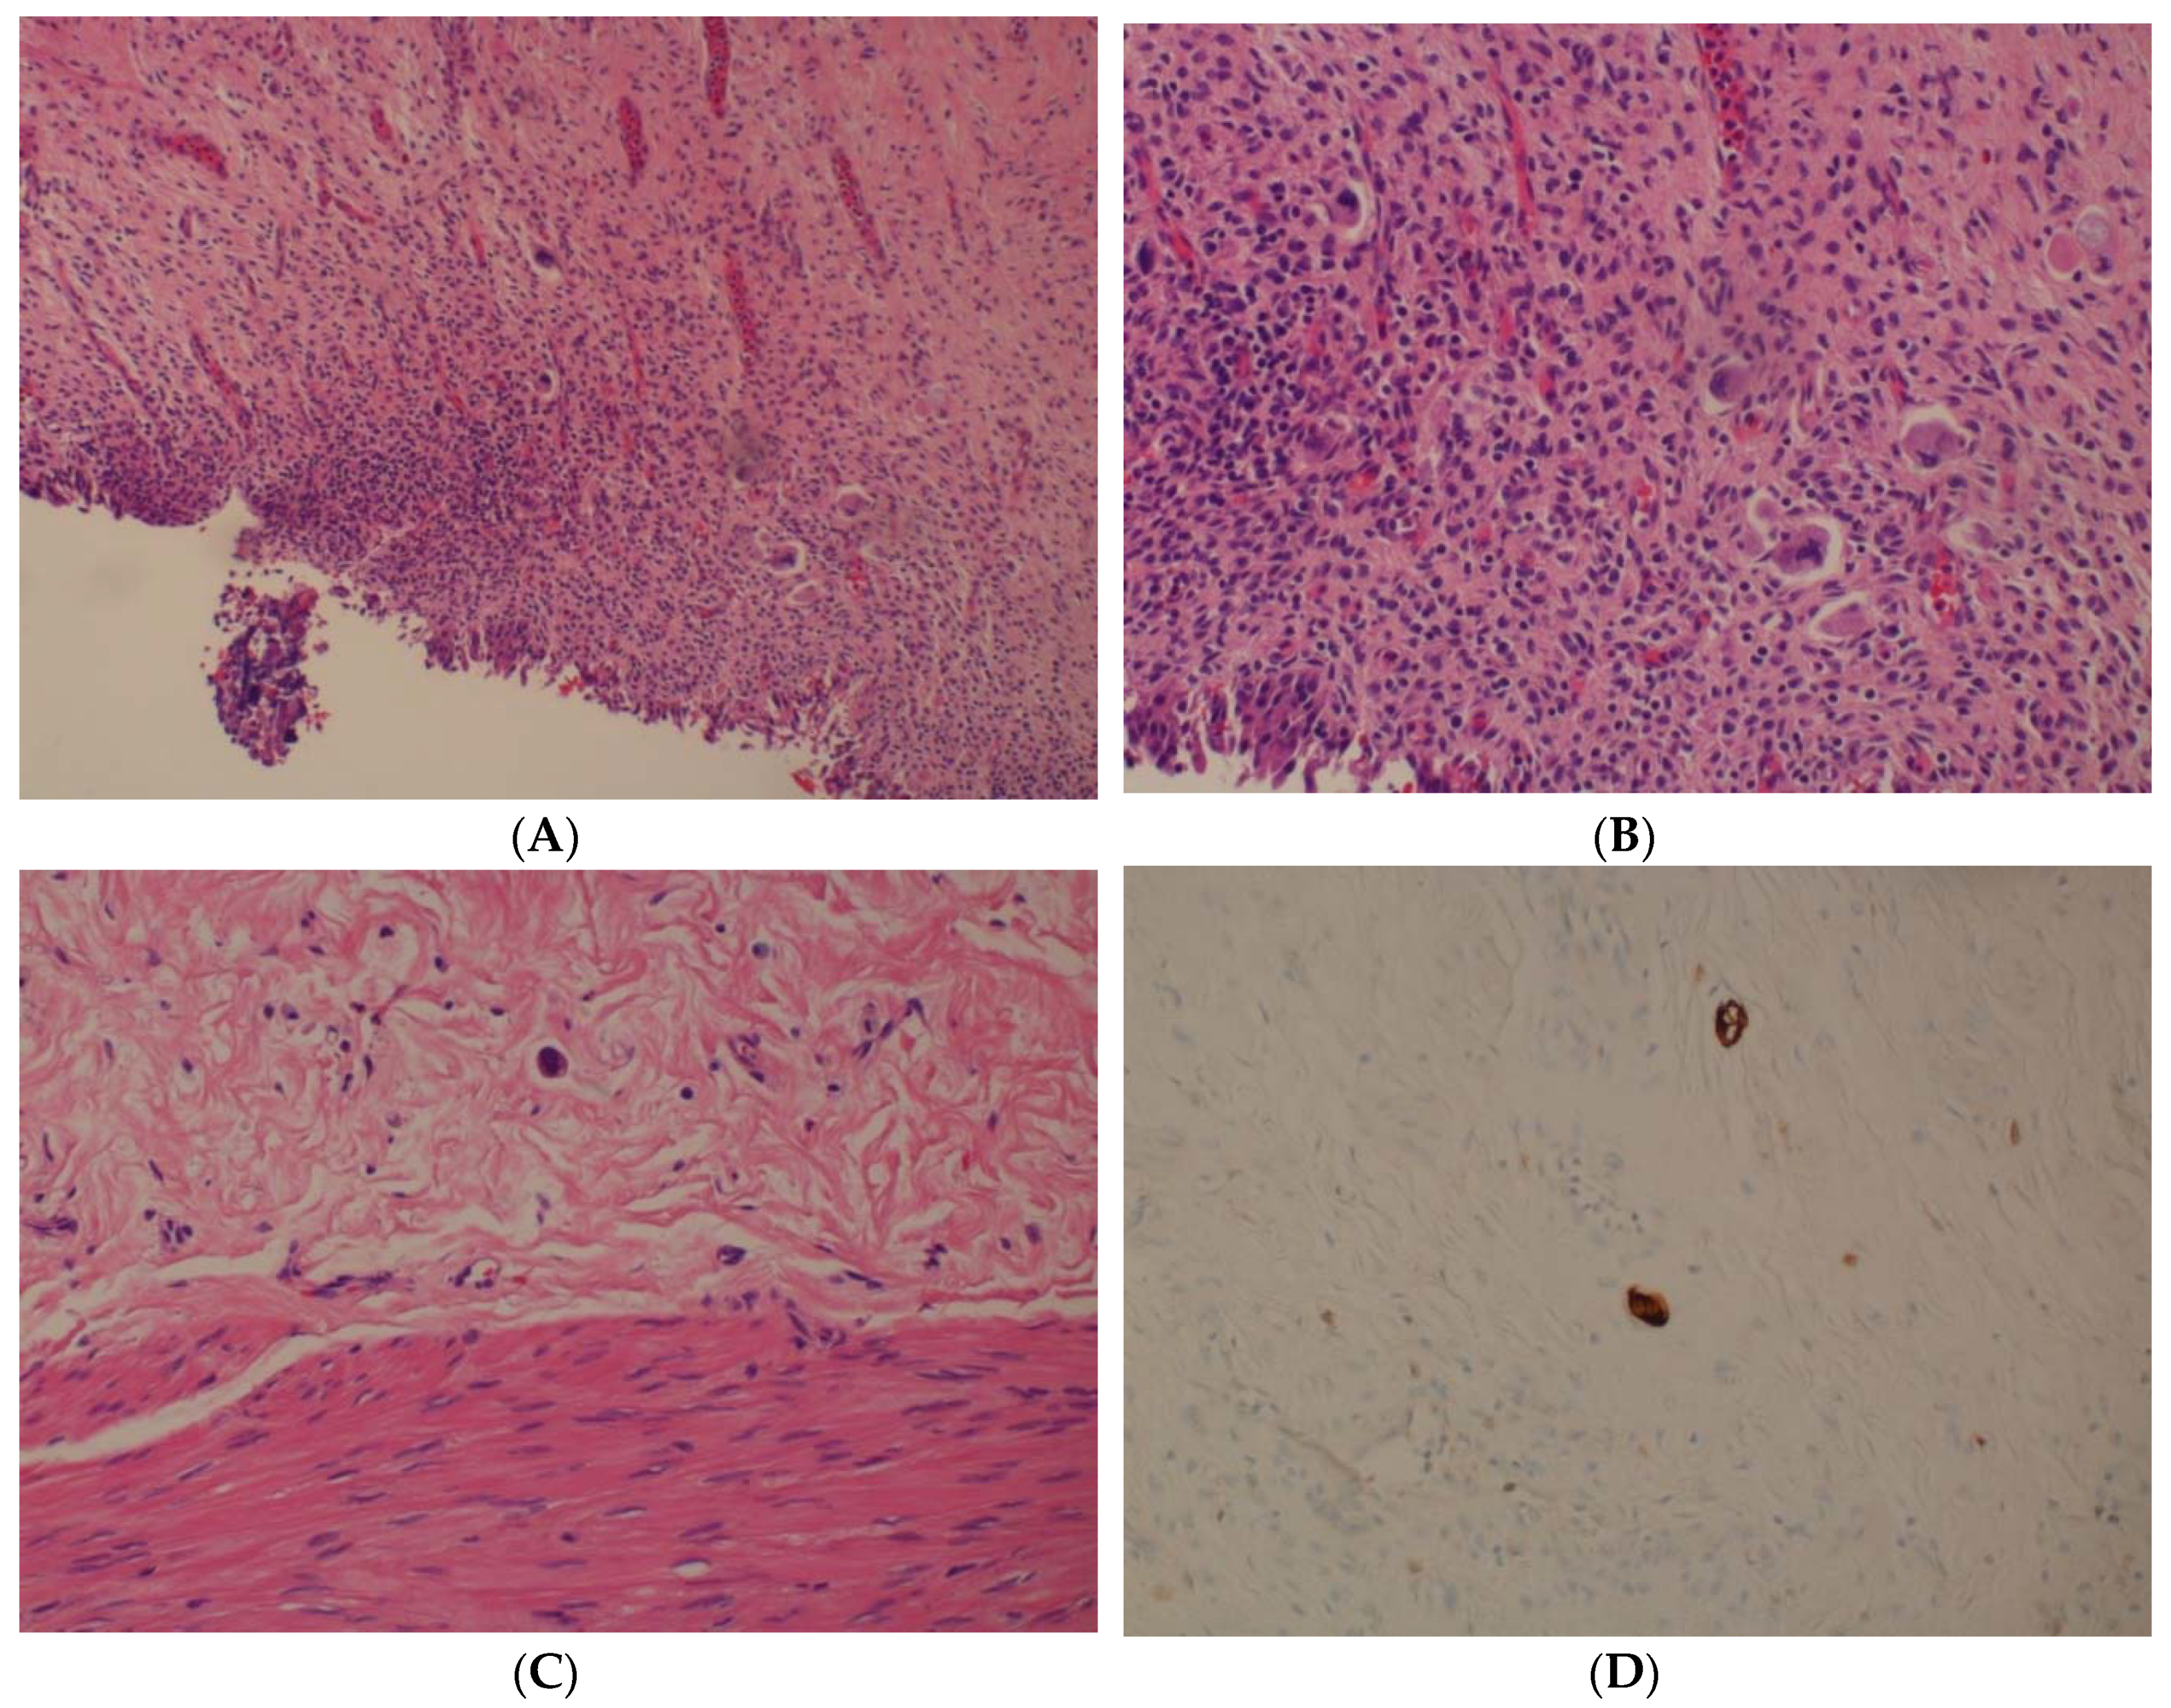

2. Case Series